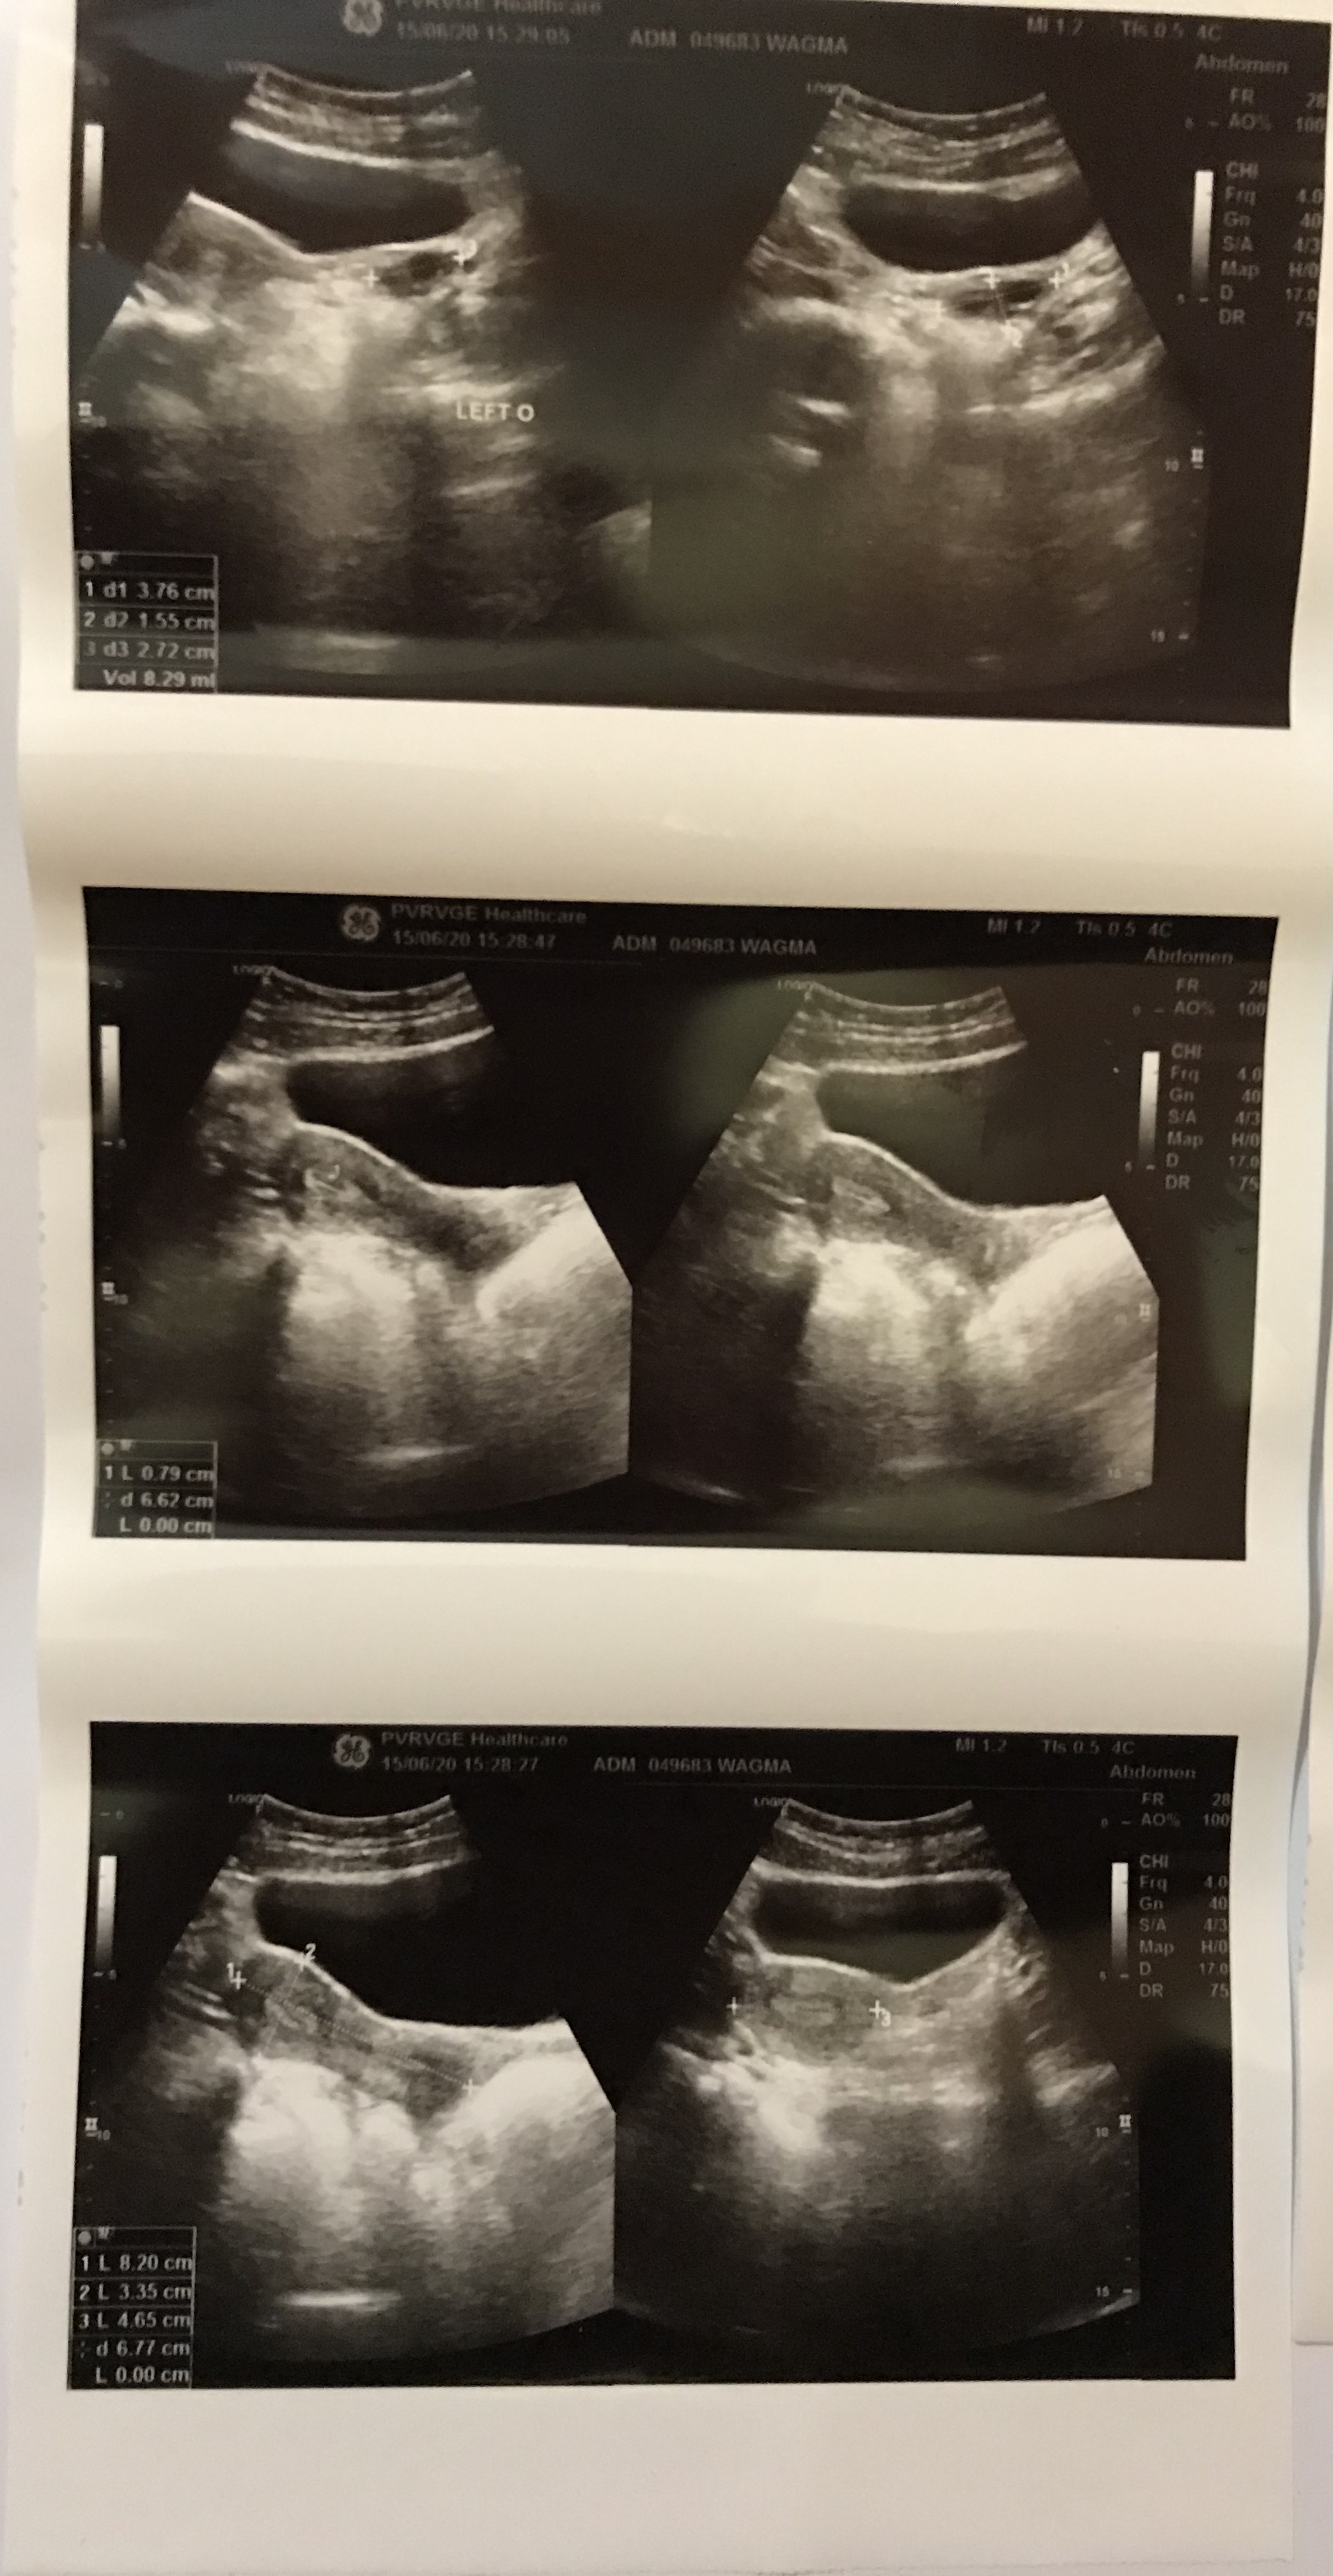

Dr i m attaching my todays pelvic ultrasound report, kindly can u tell me if its fine

#2

#3

#4

Mam i had a pelvic ultrasound just before ramadan .it was a normal ultrasound .

Can pcos emerge in 1-2months?